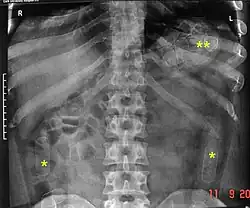

Es besteht ein großes Risiko für das Leben des Bodypackers, wenn eines der Päckchen platzt. Dabei können die giftigen Wirkstoffe der Droge austreten und über die Schleimhäute aufgenommen werden. Der Nachweis der Päckchen geschieht durch eine Röntgenübersichtsaufnahme des Bauchraums und durch Sonografie. In Sonderfällen ist eine endoskopische Bergung möglich. Ein operativer Eingriff, um die Container zu entfernen (Laparotomie), wird bei gerissenen Behältern durchgeführt sowie dann, wenn die Chance des Zerreißens als groß eingeschätzt wird.